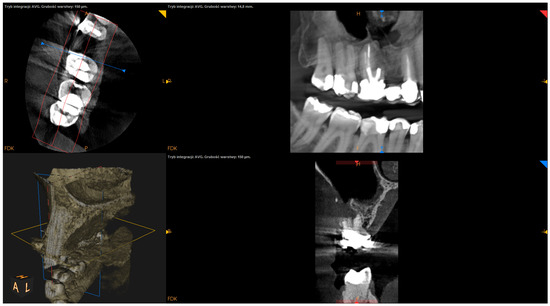

- The status of radiographic healing (rated in all sections, according to modified PENN 3D criteria [28]) was classified as complete healing (Figure 1), incomplete healing (Figure 2), uncertain healing (Figure 3), or unsatisfactory healing (Figure 4).

Figure 3. CBCT image (CS 8100 3D Carestream Dentalⓡ) example of uncertain healing based on PENN 3D criteria. Non-English annotations present software technicalities (AVG integration mode and layer thickness).